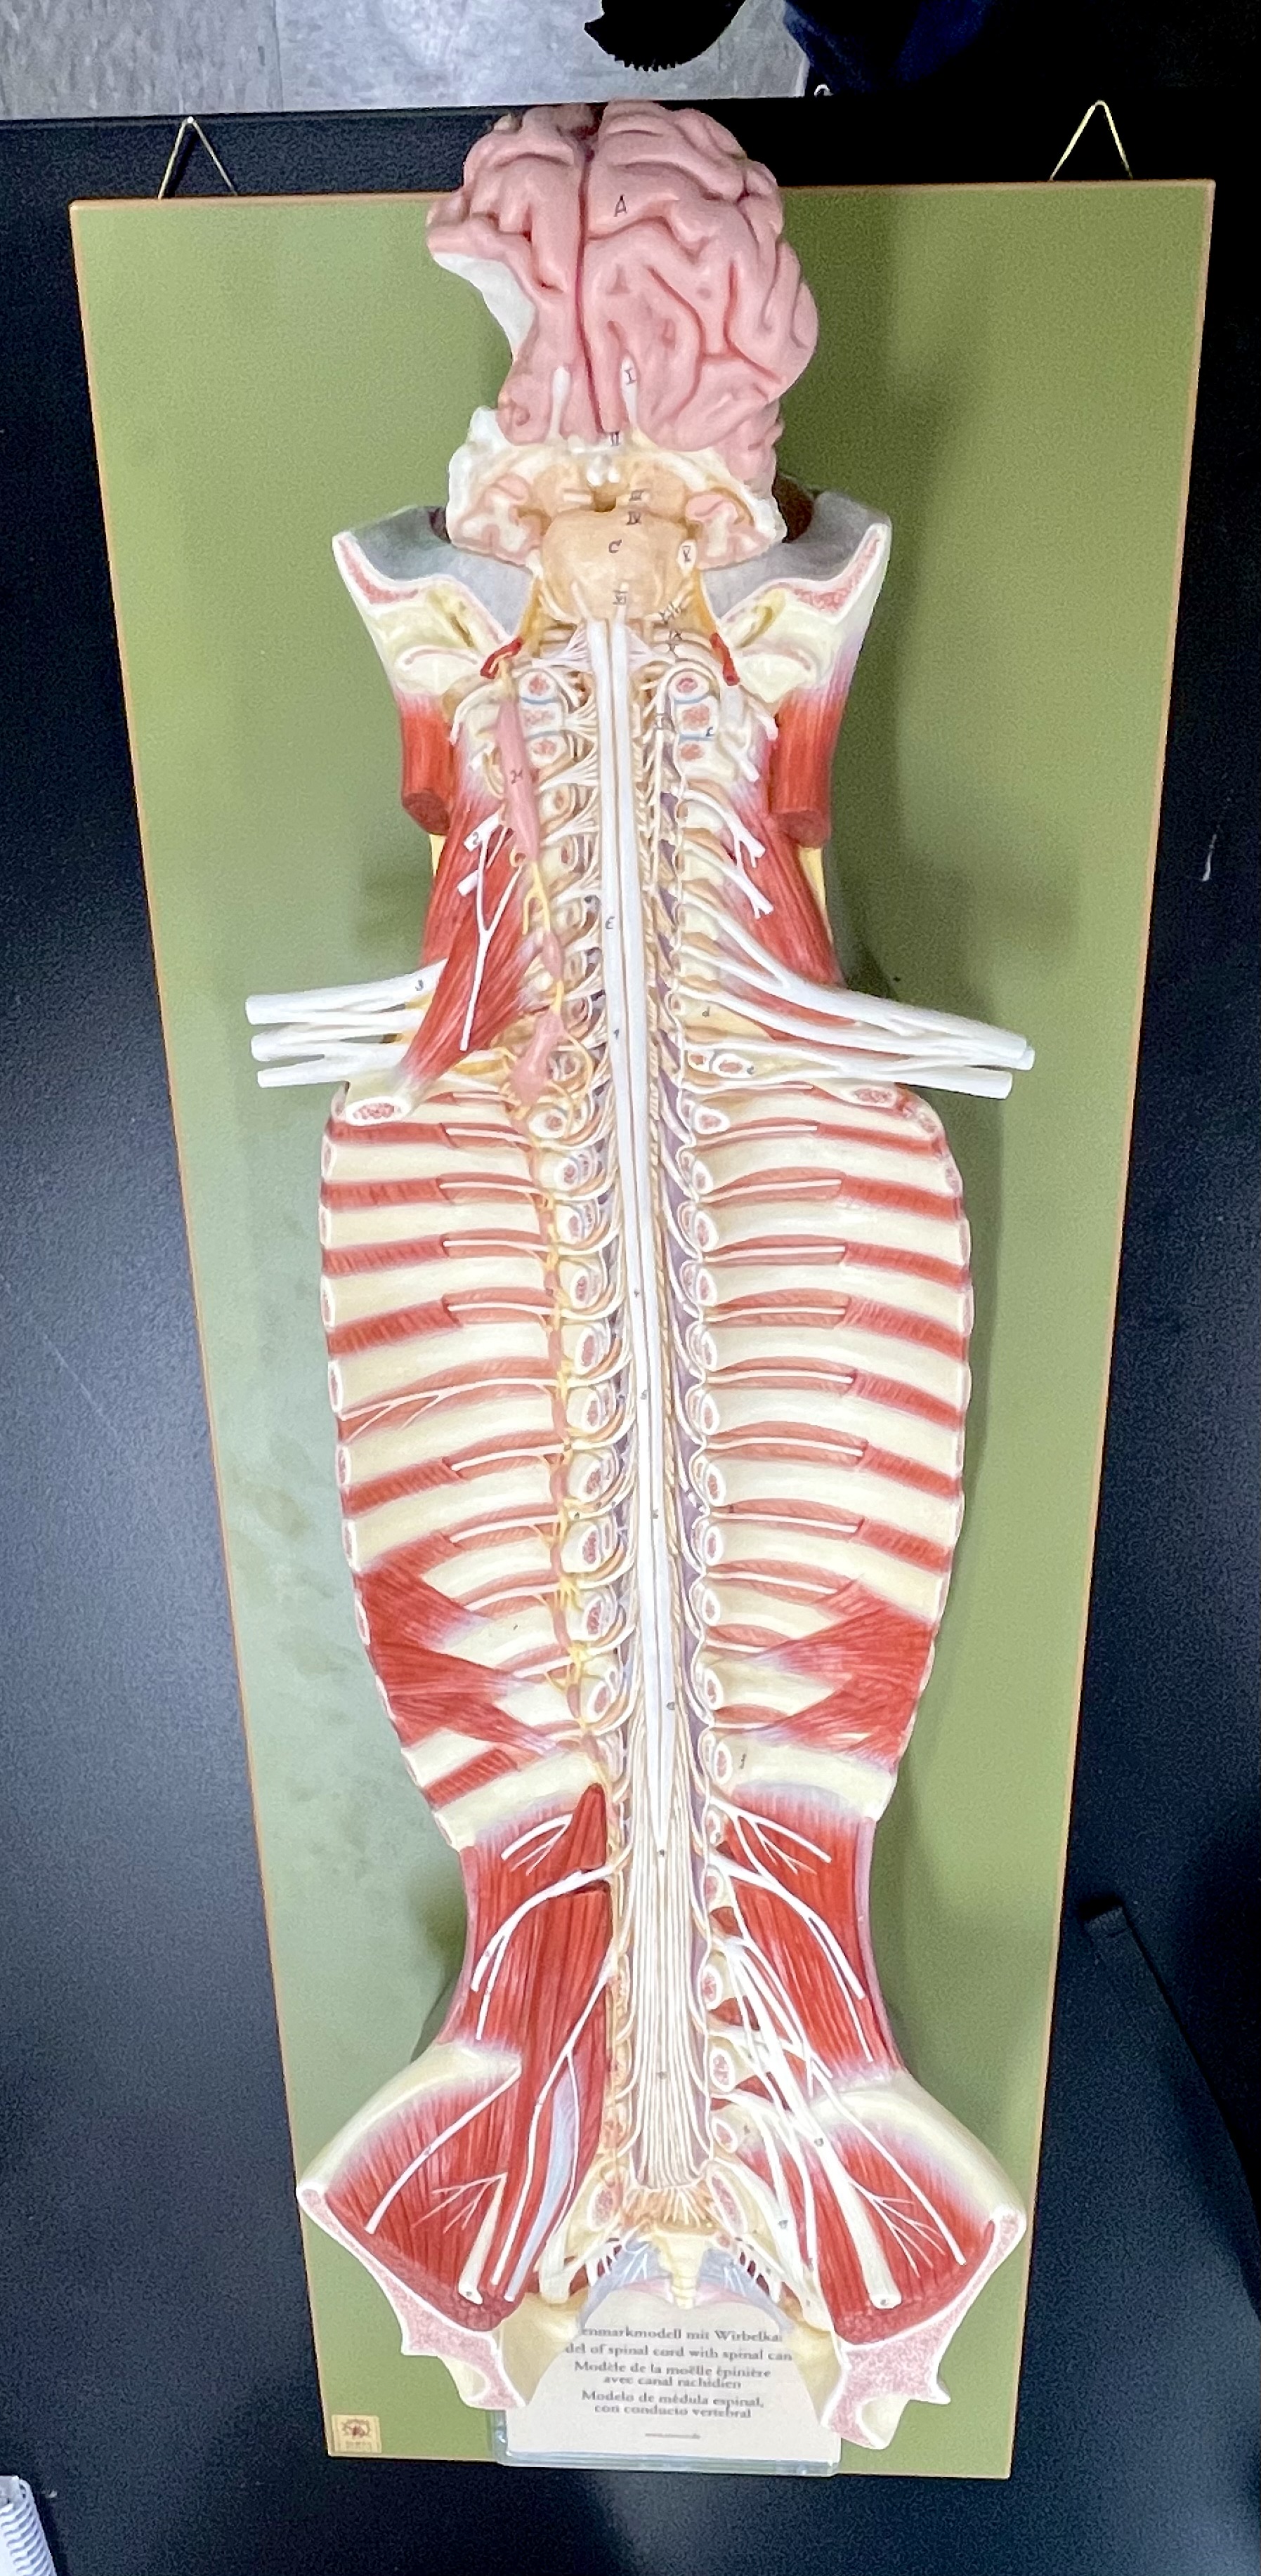

What type of spinal nerve is this? How many pairs?

cervical (8 pairs)

What type of spinal nerve is this? How many pairs?

thoracic (12 pairs)

What type of spinal nerve is this? How many pairs?

lumbar (5 pairs)

What type of spinal nerve is this? How many pairs?

sacral (5 pairs)

cervical enlargement

cervical enlargement

thoracic segment

lumbar enlargement

lumbar enlargement

conus medullaris

conus medullaris

filum terminale

cauda equina

sympathetic chain ganglia

cervical plexus – phrenic nerve

cervical plexus – phrenic nerve

brachial plexus – ulnar nerve

brachial plexus – median nerve

brachial plexus – radial nerve

lumbar plexus – femoral nerve

lumbar plexus - femoral nerve

sacral plexus – sciatic nerve

sacral plexus – sciatic nerve